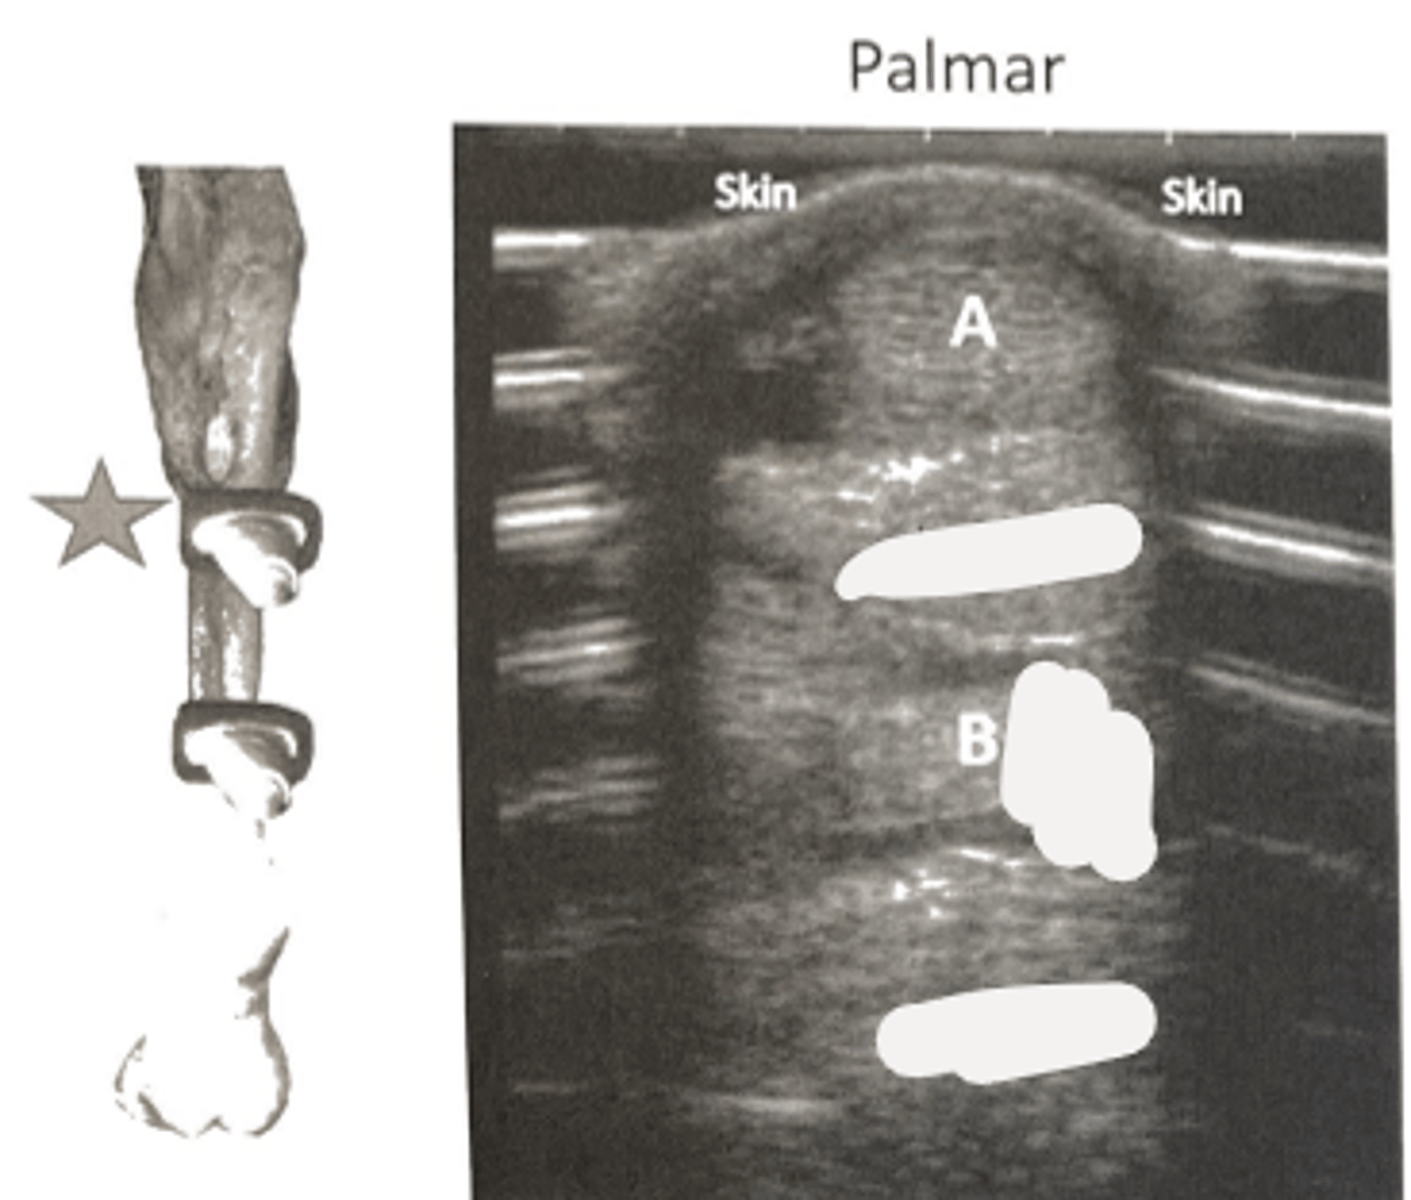

This image represents a transverse cut of the proximal one third of of the right metacarpus. Identify the soft tissue structure A:

medial splint bone (MC2)

This image represents a transverse cut of the proximal one third of of the right metacarpus. What is the laypersons term for B?

superficial digital flexor tendon

What is A?

accessory ligament of the DDFT (distal check)

What is B?